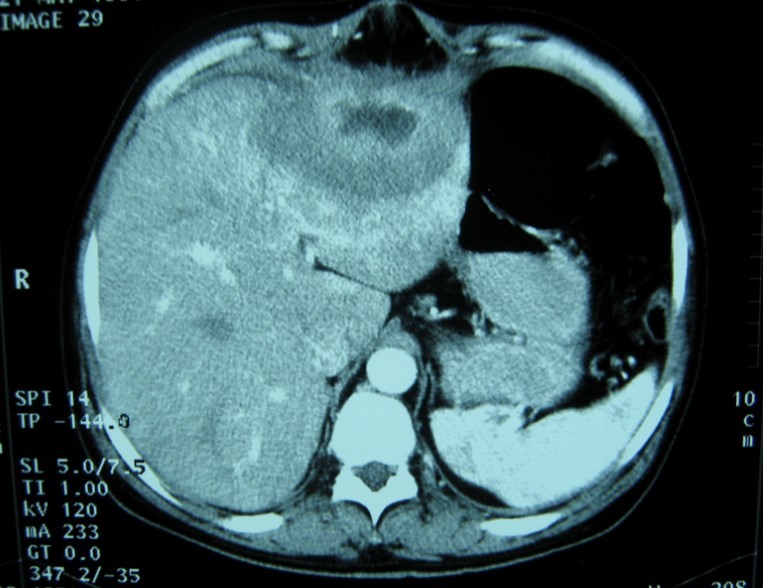

Laboratory analysis showed hemoglobin, 10.9 g/dL; white blood cell count, 9,800 cells/mm3, serum albumin, serum total bilirubin, alanine aminotransferase, aspartate aminotransferase, prothrombin time, hepatitis B surface antigen, and antibodies to hepatitis C, serum alpha-fetoprotein (AFP), carcinoembryonic antigen and carbohydrate antigen 19-9 (CA 19-9) were within normal range. Blood cultures were negative. Chest x-ray was normal. Ultrasound of abdomen showed a 10 cm hypoechogenic lesion in left liver (Figure 1). An abdominal CT showed a well-defined heterogeneous mass situated in his left hepatic lobe measuring 10 cm × 7 cm (Figure 2, Figure 3). The lesion featured central necrosis, a hyper-dense rim and a mild enrichment from the arterial phase in the CT, The diagnosis of primary hepatic tumor was suspected. An ultrasonography-guided needle biopsy of the liver was scheduled in order to rule out malignancy and to have a complete diagnosis. Cytology demonstrated a tuberculosis granuloma, acid-fast bacilli culture was positive (Figure 4). Anti-tuberculous therapy including isoniazid, rifampin, ethambutol, and pyrazinamide were prescribed. The patient completed the 6-month course of medication with success. The patient’s appetite and body weight were restored to previous levels. One year after the completion of treatment, the patient remained completely asymptomatic with disease free.

Figure 2.Abdominal computed tomography with intravenous contrast showing 10x7 cm low-density focal lesion

CT findings of tuberculosis abscesses can show low-density focal lesions with or without ring enhancement on contrast administration. These have also been seen in necrotic tumor such as hepatocellular, inflammatory disease and metastatic carcinoma 12.